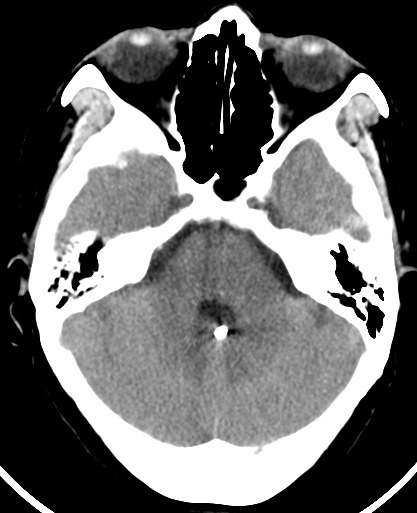

【医讯速览·新闻】第31期:颅内动脉瘤破裂,神经外科再次“拆弹”成功